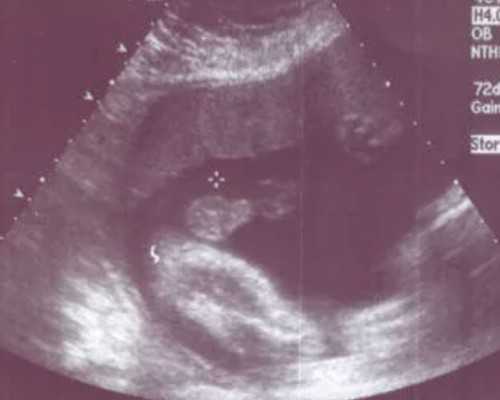

在过去大陆通常会选择B超来鉴定胎儿宝宝性别但通过B超观察宝宝生殖器官总会有许多的不利影响因素干扰比如胎儿宝宝体位不正观察不到生殖器官或者小手放在生殖器官旁都会干扰人眼识别,经常会出现翻盘的结果,而且需要孕妈妈们怀孕时间长达四五个月以后才适合做B超进行预测,而且B超预测早在许多年前就已经被大陆法律禁止,然而在香港验血检测宝宝性别是完全属于合法检测,是受到法律保护的。

第一:孕妈需要提前在大陆做好B超检查,由医生确认自身孕期满七周或者以上,胚芽长度达到10mm,这是为了保证胎儿游离的DNA浓度达到最大方便化验以及排除宫外孕等问题。